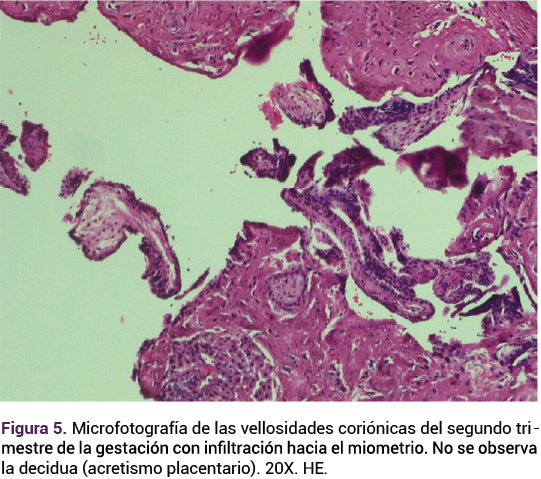

Paciente de 40 años con antecedentes de menarquia a los 15 años, 4 embarazos, 1 parto eutócico y 2 cesáreas electivas; fecha de la última menstruación no confiable, previo esquema de anticoncepción hormonal inyectable. Acudió a consulta a solicitar la interrupción legal del embarazo. En la valoración ecográfica transvaginal se observó un saco gestacional implantado a nivel ístmico-cervical, con feto vivo de 12 semanas de gestación (longitud cefalocaudal de 61 mm), con frecuencia cardiaca fetal de 145 lpm. Ante esos hallazgos se solicitó la interconsulta con los especialistas en medicina materno-fetal quienes corroboraron el diagnóstico de embarazo ectópico ístmico-cervical (Figura 1).

<strong>Figura 1</strong>

Figura 1.